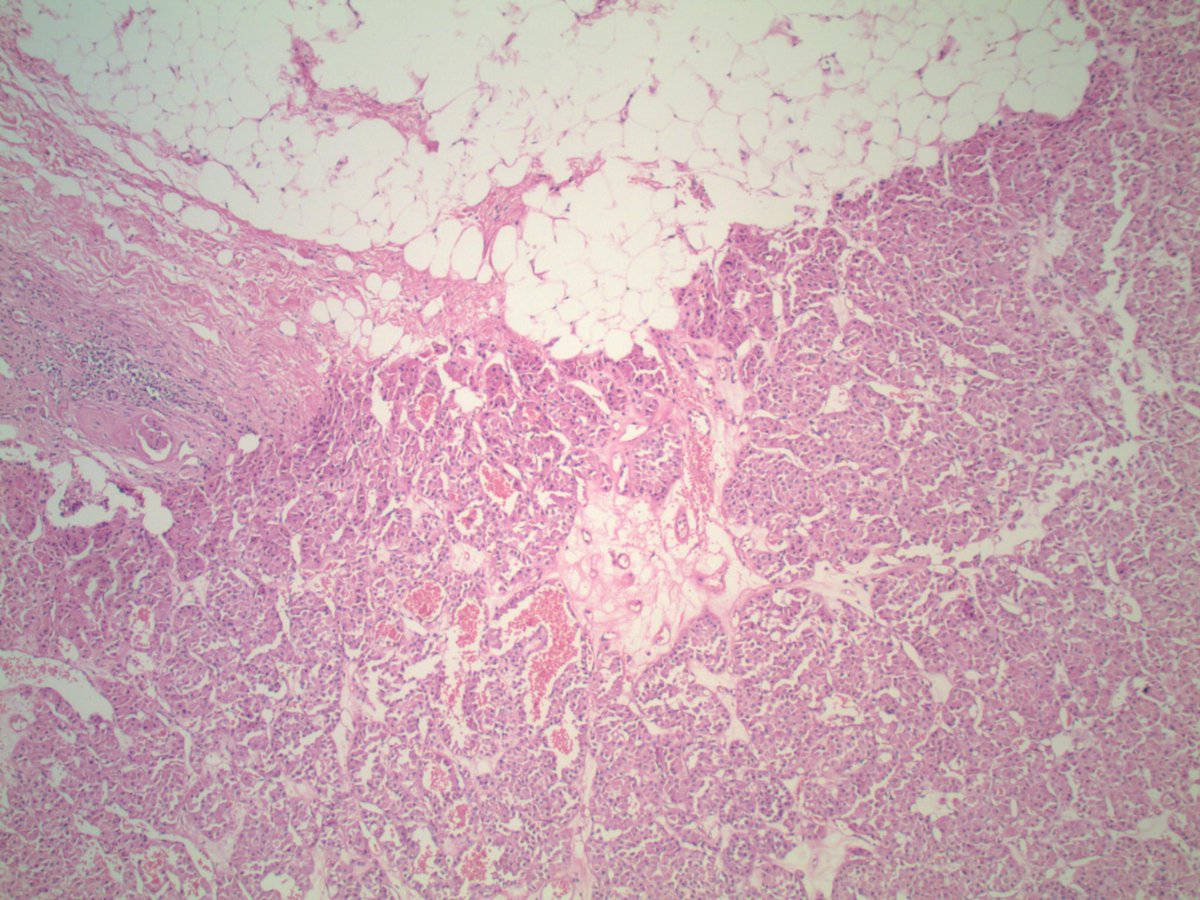

#GUpath nephrectomy: renal oncocytoma, "invading" perinephric adipose tissue ✔️does not necessarily itself portend malignancy PMID: 9255250 PMID: 21166703